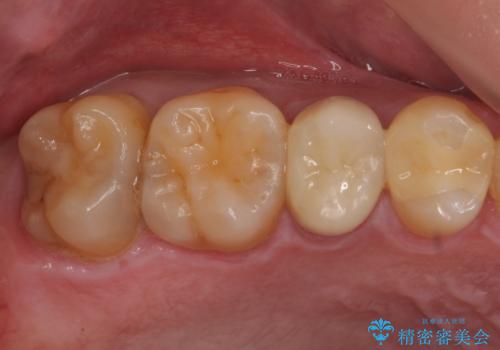

セラミック治療 → セラミックインレー

歯と歯の間によくものが詰まる。。セラミック治療

銀の詰め物を白い物にしたい